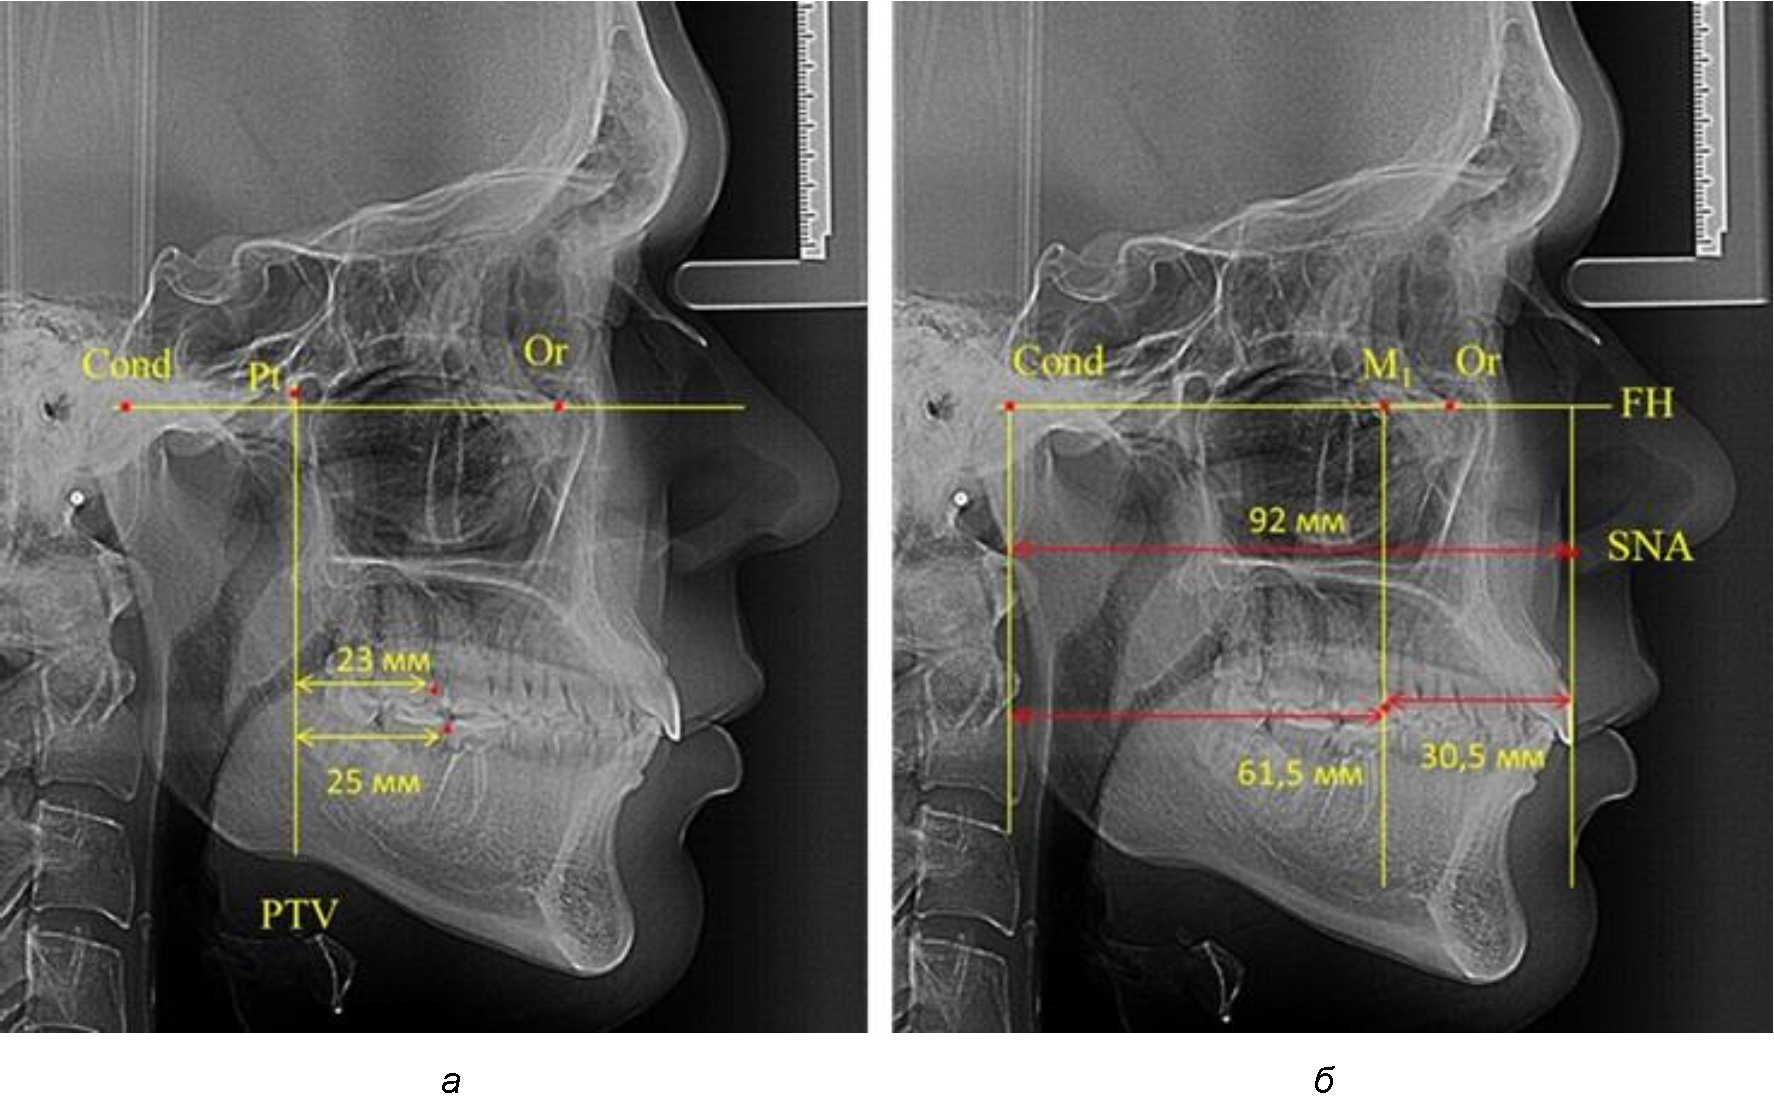

Рис. 1. Метод определения положения первых верхних моляров по Ralph E. McDonald (а) и по предложенному методу (б)

В то же время при увеличенном расстоянии от крыловидной вертикальной плоскости PTV до дистальной поверхности верхнего первого постоянного моляра, равное 23 мм, сагиттальный размер гнатического отдела составил 92 мм. При этом отношение кондилярно-спинального расстояния к кондилярно-молярному размеру (30,5), так же, как и при малых размерах, было близким к коэффициенту 1,5, что представлено на рис. 3.

Рис. 3. Особенности положения первых моляров по R. E. McDonald (а) и по предложенному методу (б) при увеличенном молярно-крыловидном расстоянии